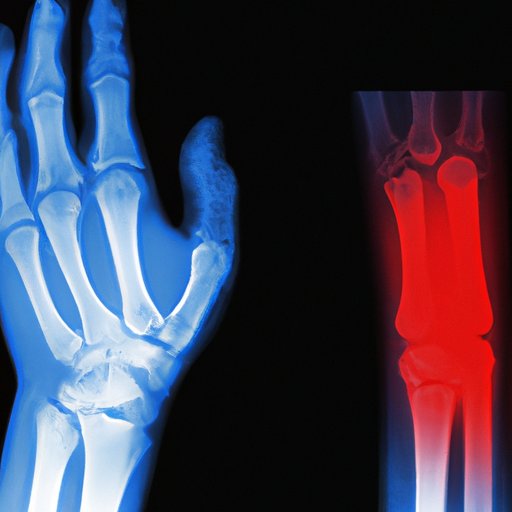

Arthritis can be a challenging condition to diagnose. This...